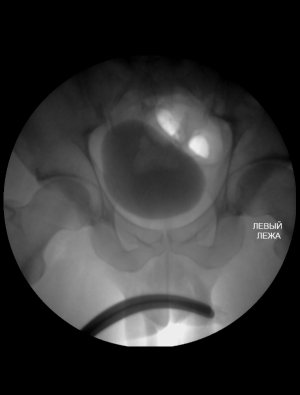

Не открываетеся. Объемные образования лучше видно при УЗИ, чем при микционной цистографии.